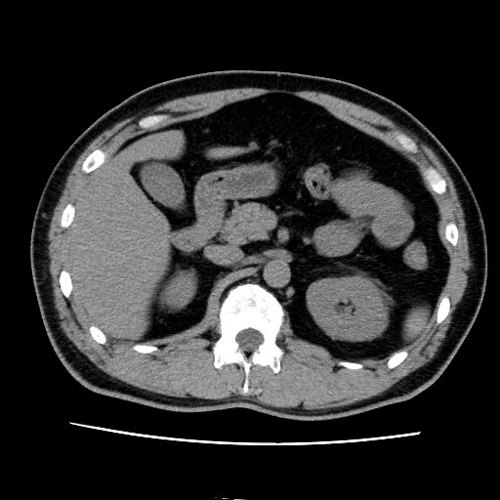

【CT(computed tomography)】

管球(ドーナツ状の部分にあるX線を出す機械)がX線を出しながら体の周りを回転し、人体を透過したX線をコンピューター処理して画像化します。短時間で広い範囲を撮影でき、様々な方向からの画像や3Dを作成します。